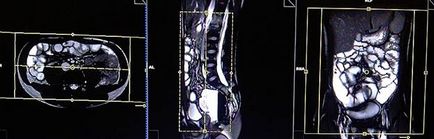

Mielőtt a következő lépést, intravénásán Buscopan 0,5-től 1 ml (per testtömeg) és 15-től 20 ml Gadolinium (súly szerint). várhatóan 1 perc (futás Buscopan akció néhány percet vesz igénybe), amíg a következő ciklusban.

Tervezés koszorúér szeletek axiális síkban; blokk helye keresztirányban hasüregben, amint az ábrán látható. Ellenőrizze a helyét a blokk a 2 másik síkon. Ezek között a szakaszok, hogy teljesen befedje a teljes hasüreget elölről hátrafelé hasfal. A látómező (FOV) elegendőnek kell lennie, hogy fedezze a has és a medence a gyomor, hogy a szint a fancsonti. Annak megakadályozása érdekében műtermékek GDV kell használni fázist túlmintavételezésre (túlmintavételezés). Fontos, hogy a beteget a levegőt-hold alatt képrögzítő csomagokat. (A mi osztály, azt utasítják a pácienseket be és ki kétszer, mielőtt „be és tartsa vissza a lélegzetét” elején a scan).

Tervezés tengelyirányú szeleteket a koszorúér síkban; blokk helye keresztirányban hasüregben, amint az ábrán látható. Ellenőrizze a helyét a blokk a 2 másik síkon. Ezek a szakaszok teljes mértékben meg kell terjednie a teljes hasüreget és a medence a gyomorból az a szint, a fancsonti. Annak megakadályozása érdekében műtermékek GDV kell használni fázist túlmintavételezésre (túlmintavételezés). Tájékoztassa a beteget, hogy lélegzet-visszatartás során képrögzítő csomagokat. (A mi osztály, azt utasítják a pácienseket be és ki kétszer, mielőtt „be és tartsa vissza a lélegzetét” elején a scan).